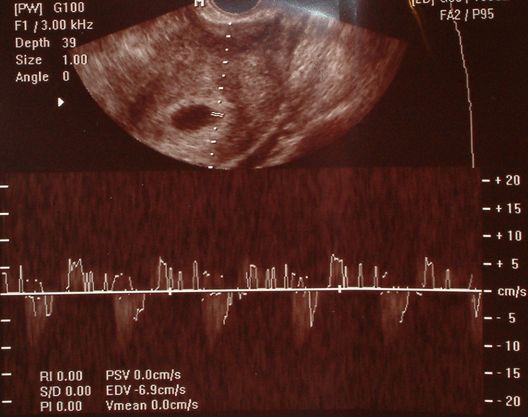

Nagyon szépen köszönöm a drukkokat! Hatásos volt!

Szerencsére minden rendben van, 20 mm-es petezsákban láttam az élő embriót és hallottuk a Férjemmel a szívhangját. A doki addig próbálta behozni, mire tökéletesen kihangosította. Persze láttuk is a monitoron a kis pulzáló szívecskét. Jajj, Lányok egy kő esett le a szívemről. A múlt heti rossz hírek után, ez mennyei érzés volt. Kaptunk képet is, amin ott van a szívritumusa is, majd megpróbálom este lefényképezni, csak most úgy elfáradtam.

5.hét vége 6. hét elején tartok. És ma reggel a hányinger engem is megkörnyékezett.

ui: jajj, majdnem elfelejtettem, hogy ikreim lehettek volna, ugyanis még egy megtermékenyített petesejtet talált a doki, de az üres volt. A doki szerint fel fog szívódni.

Az első képen a szívhang (szívritmus) látszik alul. A sötét folt pedig a petezsák és a jobb oldalán látszik valamennyire a baba, de pont olyan képet kaptam, ahol próbálta a doki bemérni a szívecskéjét, így azt a két kis vonal jelzi a képen (pzs jobb oldalt). A vonal mögött pedig a Baba. A második képen próbáltam kinagyítani, hátha meg tudom mutatni Nektek.

Kép 2009.11.16. - szívhang 5.hét vége, 6. hét eleje Kép 2009.11.16. - petezsák és a Baba

A méhösszehúzódásokat kérdezted a dokidtól, hogy mi a helyzet ilyenkor? Ha holnap mész dokihoz, akkor írd majd légyszi meg, hogy mi volt. Lehet, hogy holnap már Te is látod a szívecskéjét, egy idősek vagyunk. Csak én hajszál pontosan még nem tudom belőni, de 5. hét vége, 6. hét elején vagyok. Bár az igaz, hogy itt elég profi gépek vannak, ahol ma voltam (az én dokiméhoz képest). De remélem, Te is fogod látni/hallani holnap. Drukkolok!